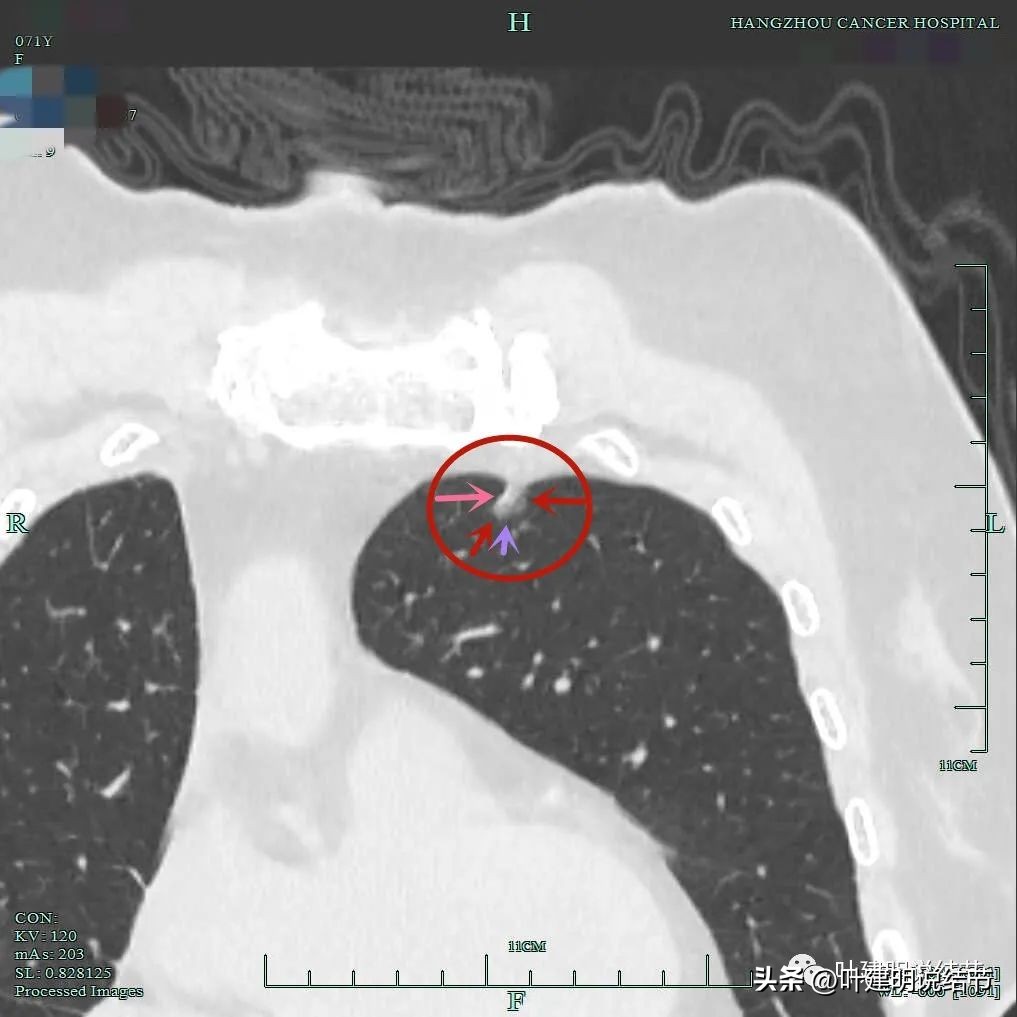

靶扫描显示主病灶混合磨玻璃密度,边缘实性成分(粉色箭头);瘤肺边界清(红色箭头);部分边缘似有毛刺(紫色箭头)。

灶内实性成分(粉色箭头)以及微血管进入(桔色箭头);整体密度不均,轮廓与瘤肺边界清(红色箭头)。